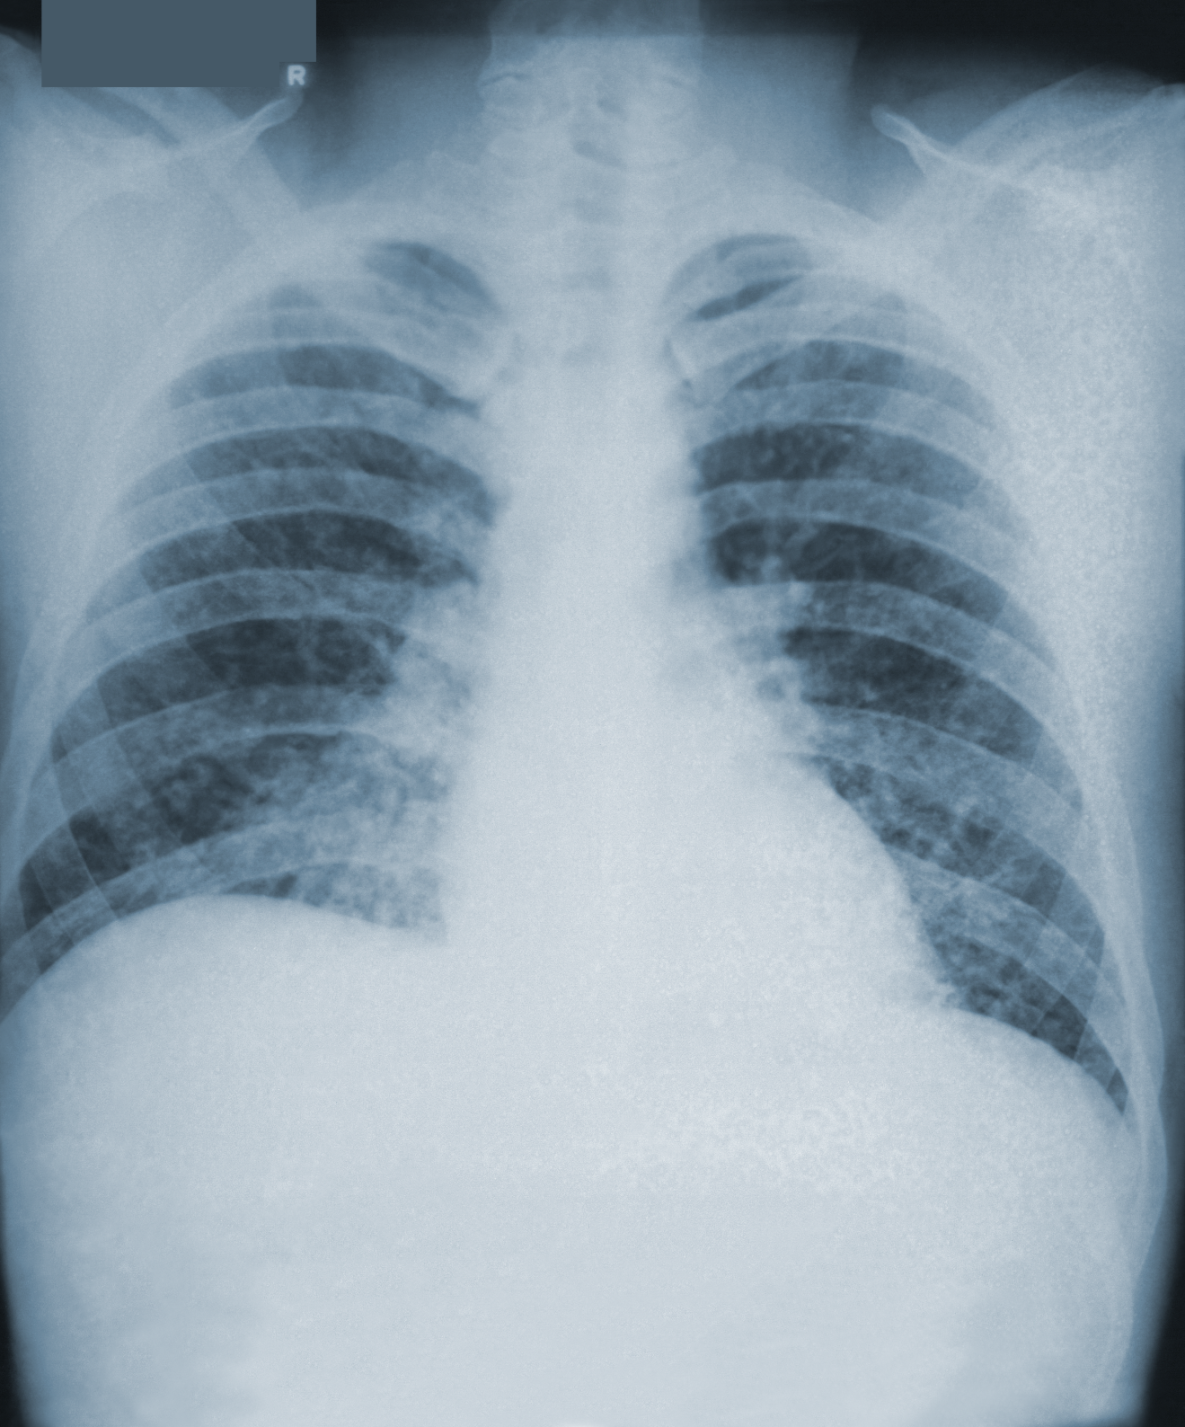

Although most people who breathe in the spores don’t get sick, those who do may have a fever, cough, and fatigue. Symptoms of histoplasmosis may appear between 3 and 17 days after a person breathes in the fungal spores. Many people who get histoplasmosis will get better on their own without medication. However, histoplasmosis can develop into a long-term lung infection. It can spread from the lungs to other parts of the body, such as the central nervous system (the brain and spinal cord).

Still, improved efforts are needed to educate the community in endemic areas about histoplasmosis to prevent the occurrence of such outbreaks in the future. In addition, increased awareness among health care providers of this disease would facilitate appropriate diagnosis and treatment as the two original cases were initially misdiagnosed with pneumonia.